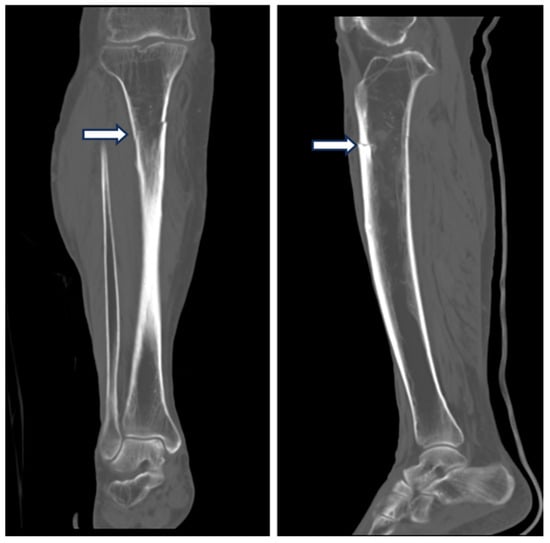

2. Case Presentation